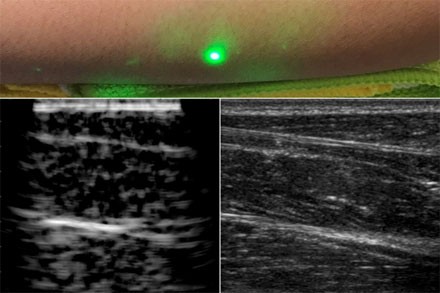

据外媒报道,12月24日,麻省理工学院的工程师设计了一种常规超声成像的替代方法,这种方法不需要与身体接触,可用于无法忍受探针进入身体的患者,如婴儿、烧伤患者或皮肤敏感的患者。在扫描志愿者前臂的试验中,研究人员能够观察到皮肤以下约5厘米处常见的组织特征,如肌肉、脂肪和骨骼。这些图像与传统的超声波相当,是使用聚焦在半米外的远程激光产生的。由于声波比光传播到体内的距离要长,因此研究人员首先研究如何在皮肤表面将激光束的光转换成声波,以便在体内成像更深。该团队选择了1550 nm激光器,该波长很容易被水吸收,并且对眼睛和皮肤都是安全的,有很大的安全边际。由于皮肤主要由水组成,因此研究小组认为皮肤应有效吸收该波长,并且它会随着反应而升温和膨胀。当它振荡回到正常状态时,可以预期皮肤会产生通过身体传播的声波。研究人员用一个1550nm的脉冲激光产生声波,用另一个调谐到相同波长的连续激光远程探测反射声波,验证了这一想法。第二个激光是一个运动探测器,它测量了声波从肌肉、脂肪和其他组织反射到皮肤表面所引起的振动。反射声波产生的皮肤表面运动引起激光频率的可测量变化,通过对全身激光进行机械扫描,研究人员能够在不同的位置获取数据,并生成该区域的图像。一种新的超声波技术利用激光在皮肤下产生图像,而不像传统的超声波探头那样与皮肤接触。新的激光超声技术被用来产生一个人类前臂的图像(左),这也是使用常规超声成像(右)。由X.Zhang等人提供。研究人员首先利用这一新的装置,将金属物体嵌入一个类似皮肤含水量的明胶模具中进行成像。他们用商业超声探头对同一明胶成像,发现两幅图像相似。然后,他们对切除的动物组织(在本例中是猪皮)进行成像,发现激光超声可以区分细微的特征,如肌肉、脂肪和骨骼之间的界限。最后,研究小组利用麻省理工学院人类实验委员会批准的方案,在人类身上进行了第一次激光超声实验。在扫描了几名健康志愿者的前臂...